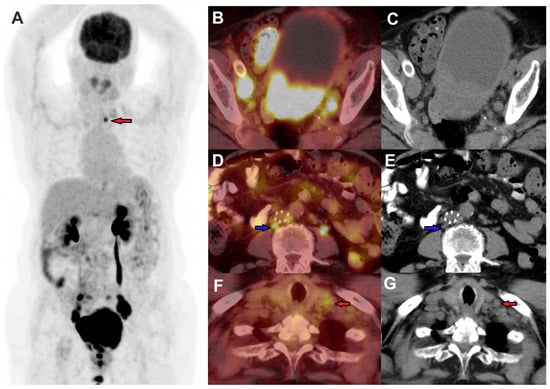

2.2. FDG PET in Recurrence

- Chu, Y.; Zheng, A.; Wang, F.; Lin, W.; Yang, X.; Han, L.; Chen, Y.; Bai, L. Diagnostic Value of 18F-FDG-PET or PET-CT in Recurrent Cervical Cancer: A Systematic Review and Meta-Analysis. Nucl. Med. Commun. 2014, 35, 144. [Google Scholar] [CrossRef] [PubMed]

- Stojiljkovic, M.; Sobic Saranovic, D.; Odalovic, S.; Popovic, M.; Petrovic, J.; Rankovic, N.; Veljkovic, M.; Artiko, V. FDG PET-CT As an Important Diagnostic Tool and Prognostic Marker in Suspected Recurrent Cervical Carcinoma After Radiotherapy: Comparison with MRI. Radiol. Oncol. 2022, 56, 453–460. [Google Scholar] [CrossRef] [PubMed]

- Lai, C.-H.; Huang, K.-G.; See, L.-C.; Yen, T.-C.; Tsai, C.-S.; Chang, T.-C.; Chou, H.-H.; Ng, K.-K.; Hsueh, S.; Hong, J.-H. Restaging of Recurrent Cervical Carcinoma with Dual-Phase [18F]Fluoro-2-Deoxy-D-Glucose Positron Emission Tomography. Cancer 2004, 100, 544–552. [Google Scholar] [CrossRef] [PubMed]

- Zhou, Z.; Liu, X.; Hu, K.; Zhang, F. The Clinical Value of PET and PET/CT in the Diagnosis and Management of Suspected Cervical Cancer Recurrence. Nucl. Med. Commun. 2018, 39, 97–102. [Google Scholar] [CrossRef] [PubMed]